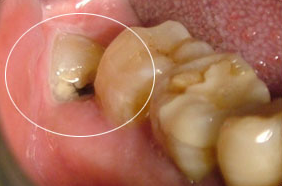

智齿肿痛怎么办?

智齿牙龈肿痛怎么办